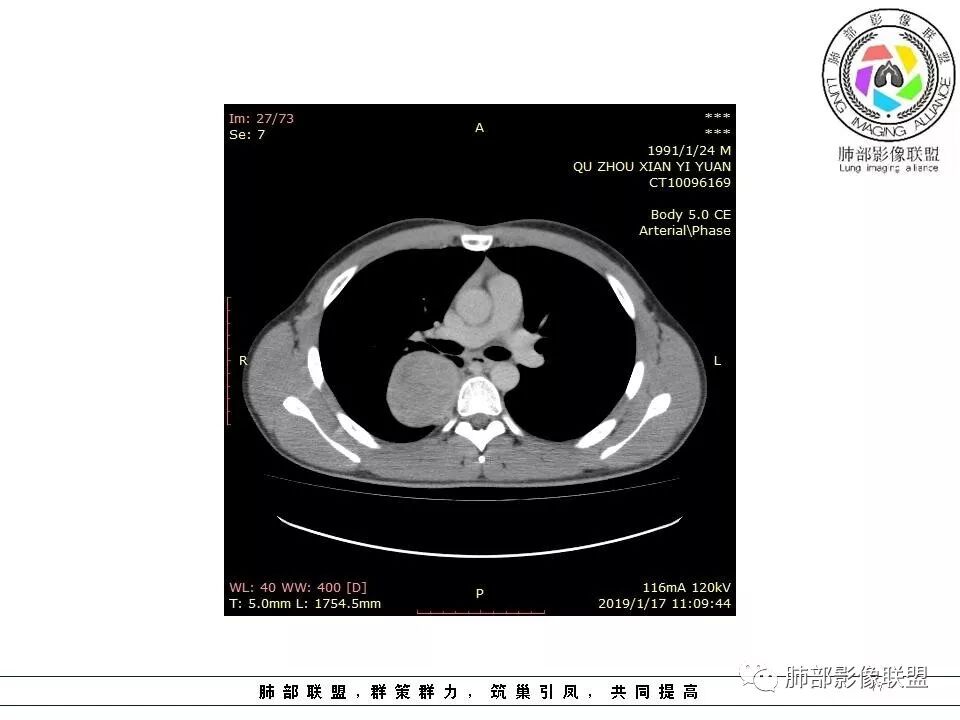

脏层胸膜主要由支气管动脉和肺动脉供血,壁层胸膜主要由支气管动脉,胸廓内动脉、肋间动脉供血

如果是肋间动脉,就不可能是脏层胸膜,可以是壁层或者纵膈

但是这个病人,肋间动脉供血吧,我倾向胸膜

看血供来源(体循环),脏层来源需要打个问号了

供血,体外供血,体循环,要么是壁层胸膜,要么胸膜外的,脏层胸膜应该是对内供血。病变里面的血管,除非是非常粗大迂曲的血管,不然,我不认为是其特点。

脏层胸膜肺内供血,壁层胸膜体外供血

肋间动脉供血,不考虑脏层胸膜,SFT还是起源脏层胸膜多

所以供血还是很重要,我觉得。

这个病人不是肺动脉与支气管动脉供血,是肋间动脉供血